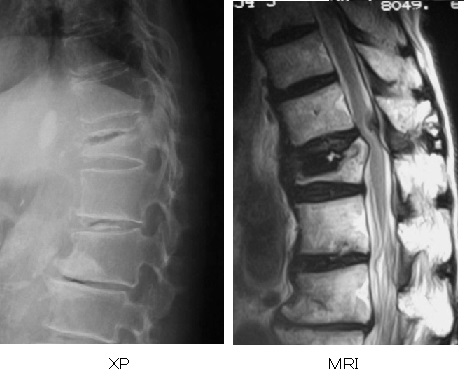

破裂骨折では、通常はレントゲンとMRIを撮影します。脊柱の破裂骨折で、圧壊が進行したり、神経症状があったりする場合、手術による固定を行います。